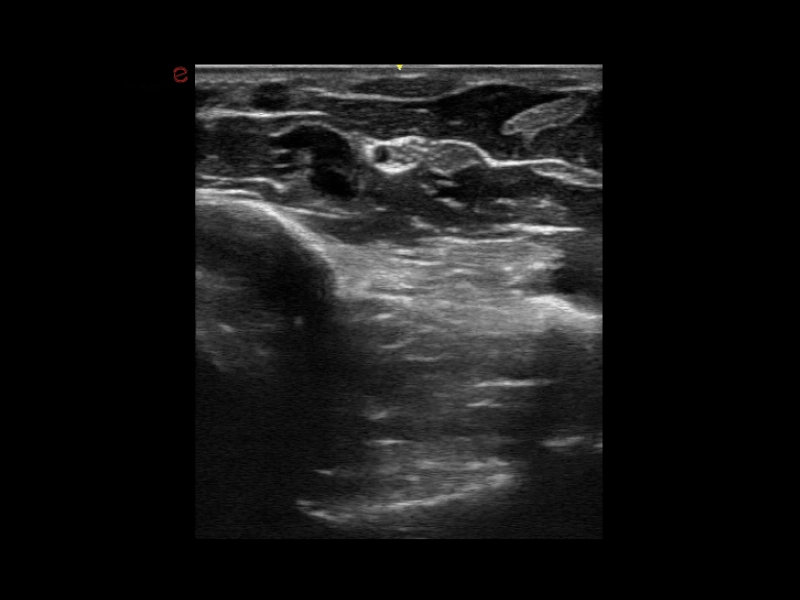

MyLab™X1 Go - Tendon

MyLab™X1 Go - Tendon

MyLab™X1 Go - Nerve

MyLab™X1 Go - Nerve

MyLab™X1 - Tendon

MyLab™X1 - Tendon